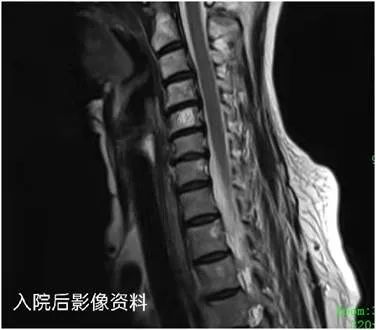

病例三:患者为62岁女性,因交通意外至骶尾部疼痛2小时急诊入院,进行查体及结合辅助检查后,诊断为1、第1尾椎椎体骨折;颈5椎体血管瘤。入院后给予对应处理后,医院骨科科组织讨论认为,结合骨折部位、骨折程度、功能恢复及对生活质量的影响程度,进行促进骨折愈合、观察病情变化等保守治疗方法。

1613706399112192.jpg

医院骨科朱崧主任认为患者颈5椎体血管瘤有头痛症状,必要时可行颈前路穿刺活检+PVP手术。陈仲教授表示,此治疗方法得当,手术指征把握准确。手术的目的是解决问题,帮助患者恢复健康,原则是先保守后手术,先救命后治病。

杨述华教授对于此次查房的三个患者病例给出了专业的指导意见:病例一患者的手术复位效果良好,胫骨平台骨折治疗不当容易引起创伤性关节炎,一定要及时指导患者功能锻炼;病例二患者手术选择时机及时有效,术式合理,需要加强石膏托固定塑性;病例三患者颈5椎体血管瘤的情况需要密切观察、每半年进行一次MRI复查,必要时行PVP手术。